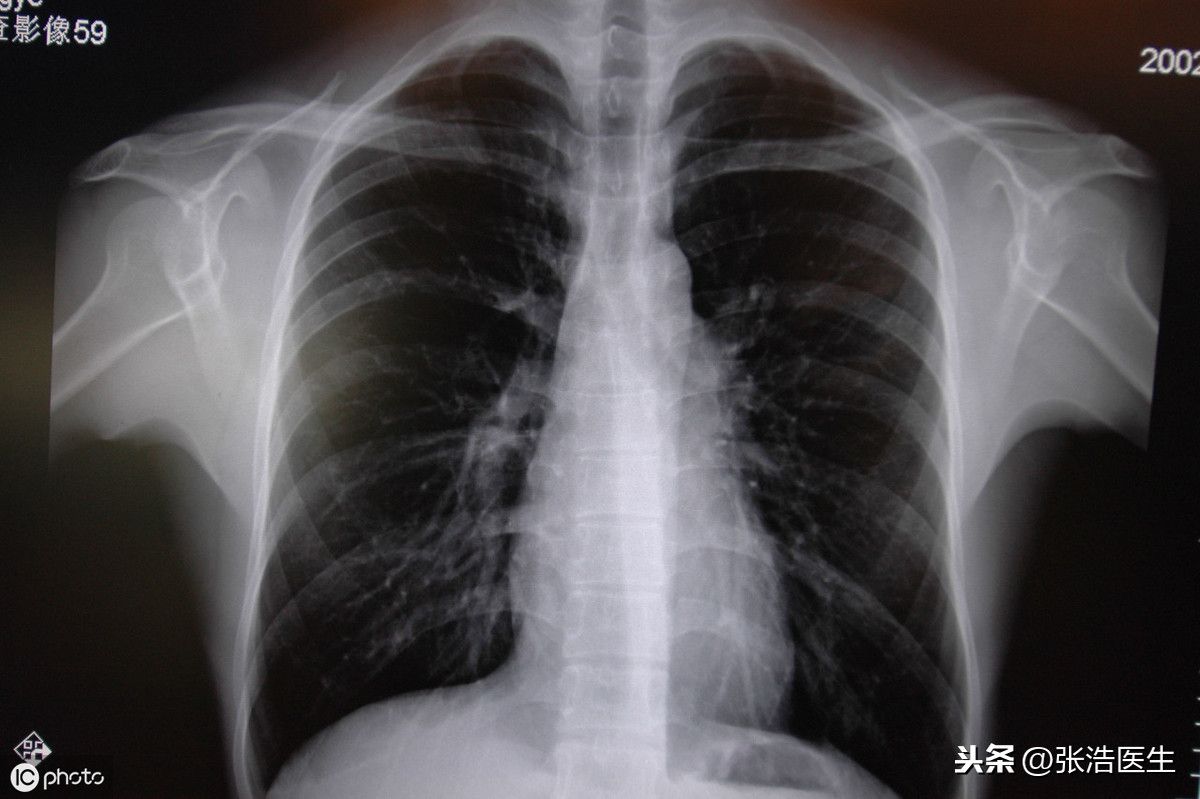

网络整理 2021-04-07 14:50右后背疼是什么原因(右后背疼会不会是肺部肿瘤?)后背疼是临床上一种常见的症状,后背疼有很多原因,要看疼痛的部位,是右侧的肩背疼还是右侧腰疼痛。

2、如果后背疼与呼吸有关,深吸气或者深呼气时疼痛加剧,那么就要考虑是呼吸系统的疾病了。